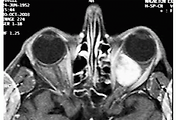

영아에서 발견되는 영아 모세혈관종, Infantile Capillary Hemangioma영아에서 발견되는 영아 모세혈관종, Infantile Capillary Hemangioma